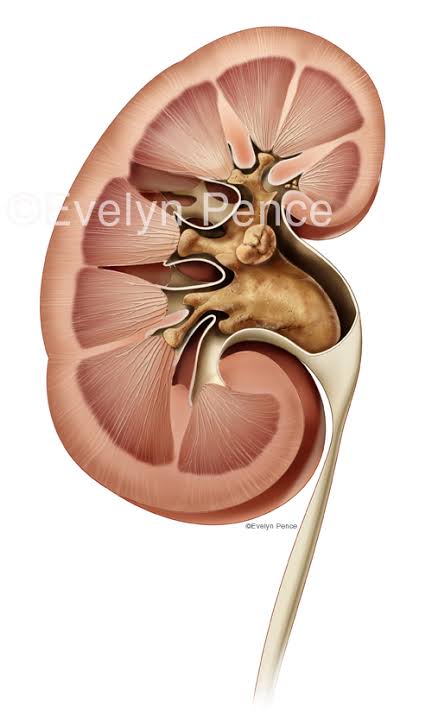

この腎盂いうとこ目一杯詰まってるってことやんな?

この腎盂いうとこ目一杯詰まってるってことやんな?

腎臓で型取りしてて草

アリの巣に流し込んで型取るやつだろ

54 風吹けば名無し 2022/04/13(水) 01:01:35.62 ID:3IS5jfn+0

65 風吹けば名無し 2022/04/13(水) 01:04:16.76 ID:3IS5jfn+0